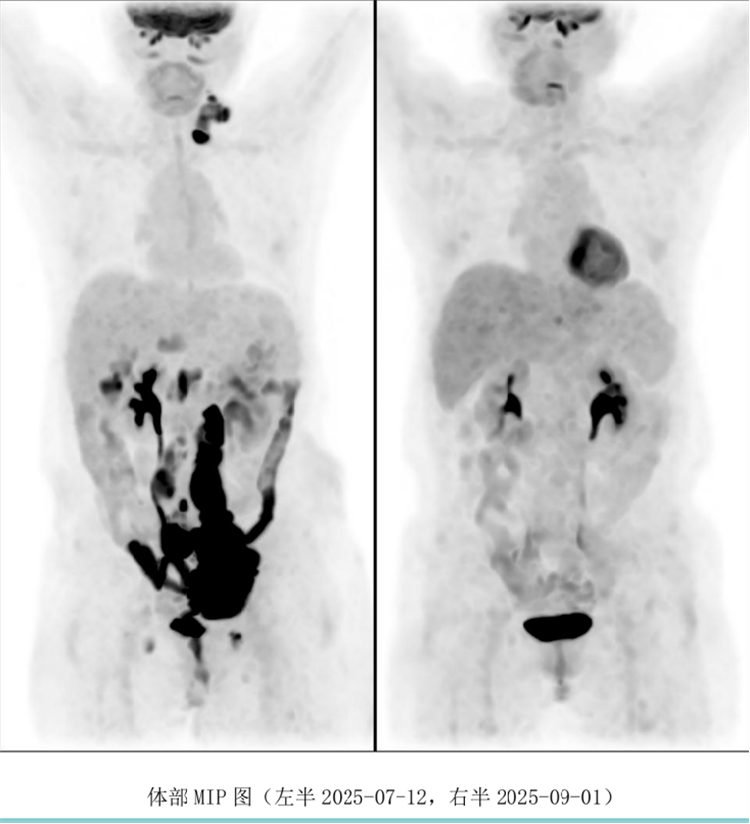

病例汇报环节由我院淋巴瘤科张薇医生带来了三例精彩纷呈的难治复发弥漫大B淋巴瘤CAR-T治疗的病例。

病例过程跌宕起伏,从桥接治疗到靶点的选择,并发症的处理都极具代表性。张医生详尽分享了患者在治疗过程中的挑战、决策依据以及CAR-T细胞治疗后的惊人缓解与转归,充分展示了CAR-T技术为晚期患者带来的突破性生存希望。